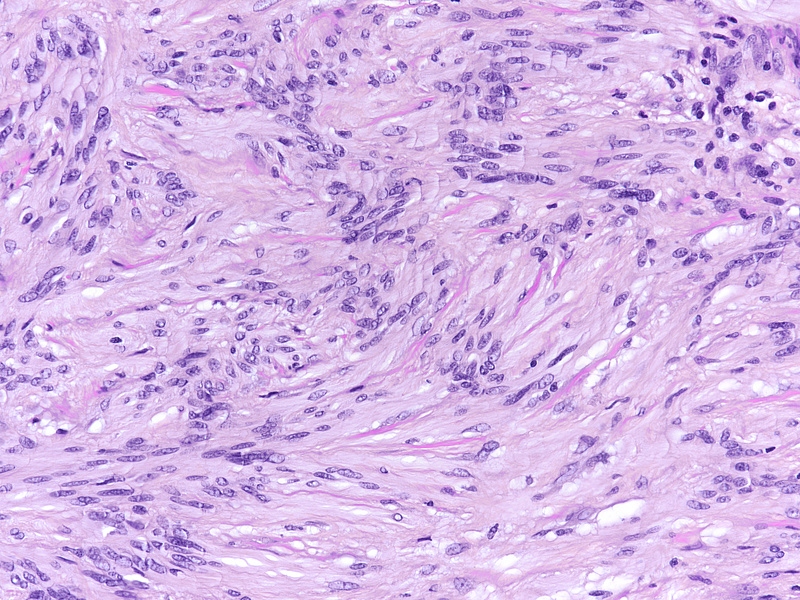

During laparoscopic surgery, the tumour proved to be confined to the appendix, with no other intra-abdominal findings (Panel A). The resection specimen disclosed a well circumscribed solid tumour, 4.2 cm in maximum diameter, with a homogeneously yellowish-white cut surface (Panels B and C).  Histologically, we observed a loose to densely cellular, spindled-cell neoplasia, arranged in fascicular and sweeping patterns (Panel D). Lymphoid aggregates, sometimes forming lymphoid follicles with germinal centres, were  found distributed at the periphery and also throughout the tumour (Panels E and F). The neoplastic cells had sparse cytoplasm and elongated, bland nuclei with inconspicuous nucleoli; focal and moderate atypia was noted (Panel G). Mitotic activity was <5mitoses/10HPF. Haemorrhage or necrosis were not observed. Upon immunohistochemistry, there was diffuse and strong positivity for S100 protein (Panel H) and moderate positivity for GFAP (Panel I). CD117 marked intralesional mast cells, whereas the tumour cells were negative (Panel J). Desmin and smooth muscle actin were negative (not shown).

The characteristic morphology directs to the correct diagnosis: a well-circumscribed lesion, with a marbled appearance due to densely cellular areas alternating with densely cellular areas; and neoplastic spindled cells, sometimes with focal, degenerative atypia. Lymphoid cuffs, usually present in soft tissue schwannomas, have an unclear aetiology; in the appendix, its presence probably is due to remnants of local MALT-tissue. Long fascicular pattern, an epithelioid appearance, tumoral necrosis and increased mitotic activity must raise concern for malignant transformation to MPNST.